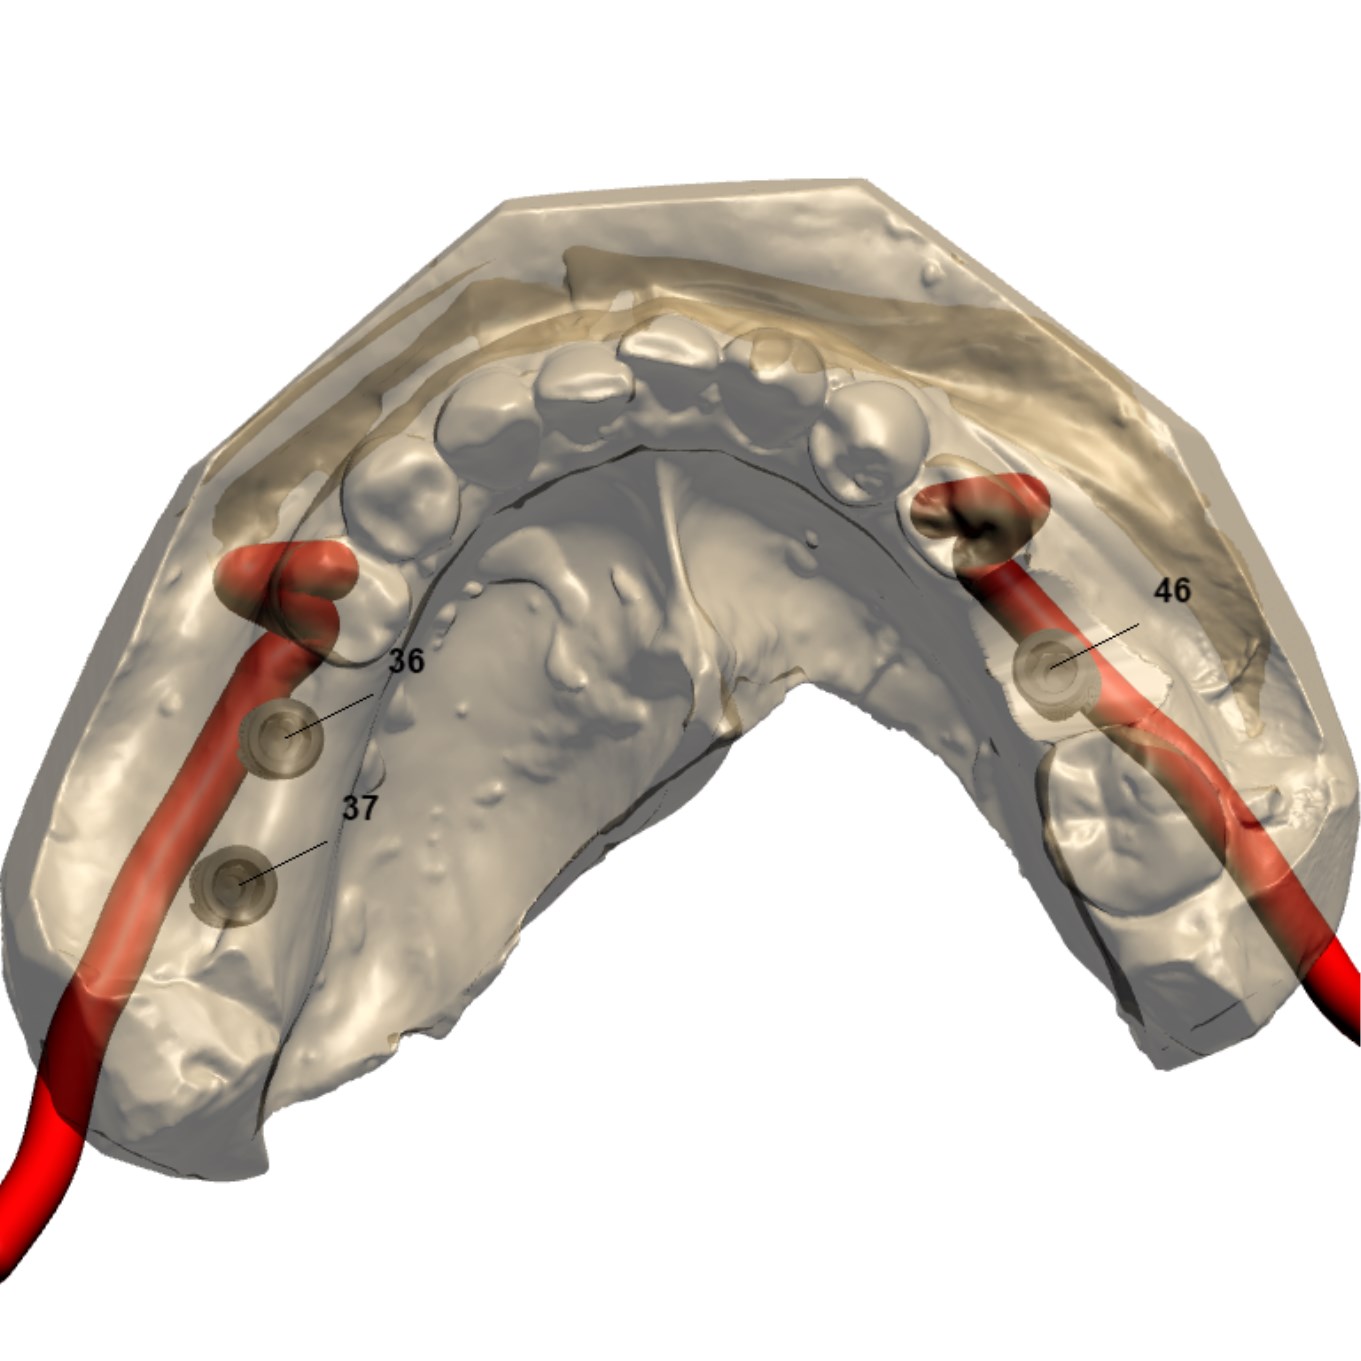

主訴

前歯がグラグラしてきた

診断

臼歯部支持の喪失に伴う前歯部への過大な咬合負担

および上顎洞底の高度な歯槽骨吸収

治療方針

前歯部の動揺は、臼歯部での垂直的な咬合支持の欠如により、前歯部へ過大な負担が集中していることが原因と考えられた。

臼歯部には既存補綴装置が装着されていたが、十分な咬合支持が得られていなかったため、インプラントによる咬合再構築を計画した。

また、上顎洞底の骨吸収が高度であったため、インプラント埋入に先立ち両側サイナスリフトを行い、十分な骨量を確保した上でインプラント埋入を行う方針とした。

患者は外科的侵襲に対する不安が強かったため、最終的にはフラップレスでのインプラント埋入を計画した。

治療内容

両側サイナスリフト

フラップレスインプラント埋入(4本)

治療期間

約6〜8ヶ月(骨成熟期間を含む)

治療費用

1,600,000

結果

十分な骨造成が得られ、フラップレスによる低侵襲なインプラント埋入が可能となった。術後経過も良好で、咬合支持の再構築による機能回復が得られている。

治療の

リスク

シュナイダー膜の穿孔、上顎洞炎、骨量不足により追加処置が必要となる可能性

考察

高度な骨吸収症例では、インプラント埋入と同時に骨造成を行う方法も選択肢となる。 本症例では骨量の確実な獲得と安全性を優先し、サイナスリフトを先行する段階的治療を選択した。

その結果、十分な骨量が確保され、最終的にフラップレスによる低侵襲なインプラント埋入が可能となった。外科的侵襲を可能な限り抑えながら、安全性と長期的安定性を両立した治療につながった症例である。